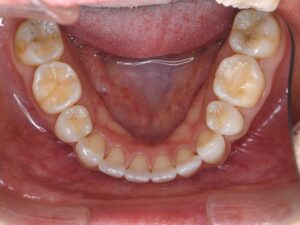

初診時CT。根管治療を何度も繰り返し行ったことで、歯根は無駄に削られて歯質が薄くなり、歯根の先端には穿孔(パーフォレーション)を生じていた。根尖病巣は認めない。

再根管治療後レントゲン。多少の違和感はあったものの、根管内部がきれいになり、排膿を認めないことから根管充填(薬を詰めること)を行った。根尖部までしっかりと薬が詰まっているのが分かる。歯根の内部がきれいな状態であれば、歯科医にはそれ以上出来ることはない。悪戯に弄り過ぎてはいけない。

同CT画像。ファイバーコアで土台を補強し、仮歯の状態で3か月の経過観察を行った。初診時にあった歯の違和感は完全に消失したため、オールセラミックで補綴処置を行うこととした。